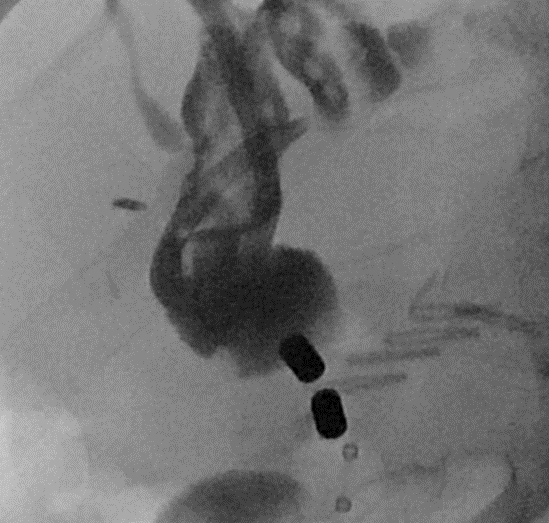

Immagine radiologica dei magneti in fase di attrazione

Nel trapianto di fegato la via biliare del donatore viene suturata a quella del ricevente (anastomosi): il restringimento di questa zona suturata è la complicanza più frequente (oltre il 10%) e avviene per un eccesso di cicatrizzazione. Dopo l’insuccesso nel superamento della ‘stenosi dell’anastomosi biliare’ con metodi endoscopici e radiologici “convenzionali”, l’equipe multidisciplinare guidata dal professor Guido Costamagna, Ordinario di Chirurgia Generale all’Università Cattolica e direttore dell’Unità Operativa di Endoscopia Digestiva Chirurgica del Gemelli, ha posizionato nelle vie biliari, a monte e a valle della stenosi, due piccoli magneti: quello inferiore tramite endoscopia e quello superiore attraverso il fegato, dopo puntura delle vie biliari dalla cute, in contemporanea. I due magneti, attraendosi, hanno determinato, in un paio di settimane, la riapertura (ricanalizzazione) del tratto biliare completamente occluso per compressione del tessuto cicatriziale, permettendo la successiva inserzione di protesi di plastica multiple per mantenere aperto il canale.

Il passaggio della bile, chiuso da una cicatrice invalicabile, è stato riaperto dalla forza di due piccoli magneti, che attraendosi l’un l’altro hanno ristabilito la continuità del dotto. L’intervento urgente e mini-invasivo di ricanalizzazione di una stenosi (restringimento) ‘invalicabile’ è lo straordinario traguardo clinico raggiunto nonostante l’emergenza Covid-19.